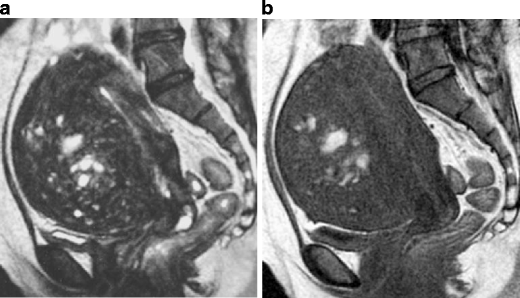

A huge subserosal leiomyoma in a 40-year-old woman. a Sagittal T2-weighted image demonstrates a huge heterogenous tumor consisting of cystic components of bright intensity anteriorly (arrows) and solid component of intermediate to low intensity. Note the tumor vessels extending from the myometrium to the tumor (arrowhead)

Red degeneration in a 36-year-old woman. a Sagittal T2-weighted image demonstrates a well-defined myometrial mass of low intensity, associated with thick rim of distinct low signal intensity (arrows). b T1-weighted image reveals entirely increased intensity in the tumor, suggesting red degeneration